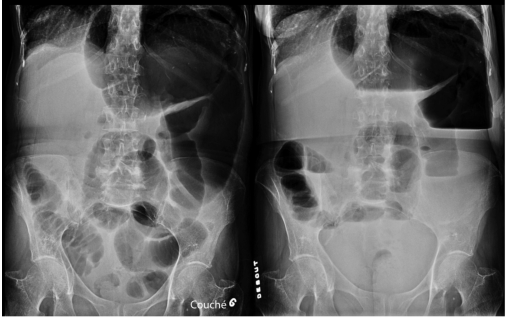

diagnostic

A

graine de café

VOLVULUS du SIGMOIDE